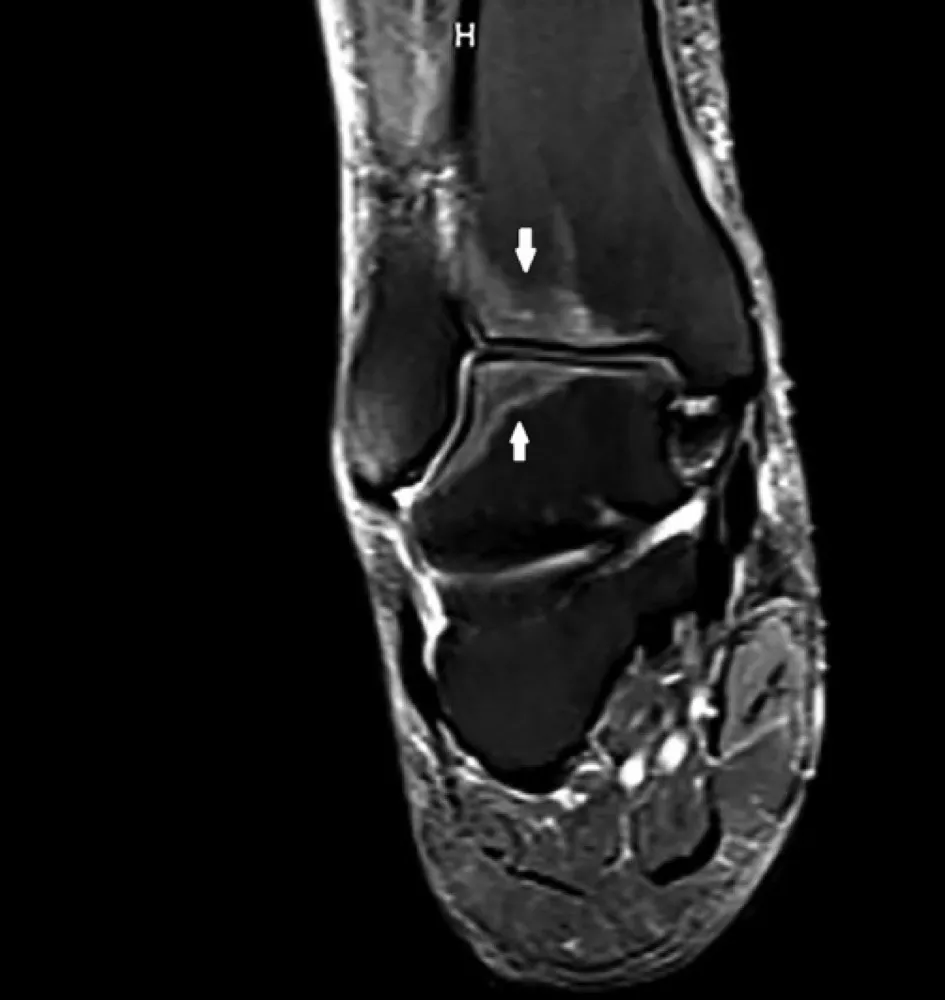

Dores em membros inferiores em um transplantado renalDores ósseas podem ser de difícil identificação etiológica. Confere esse caso clínico com uma causa atípica de dor em transplantado renal

Valkercyo Feitosa